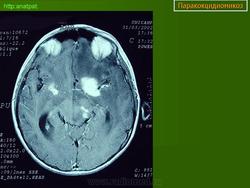

ГМ. Паракокцидиомикоз. +

Паракокцидиомикоз.

Множественные "узловые образования" имитирующие метастазы.